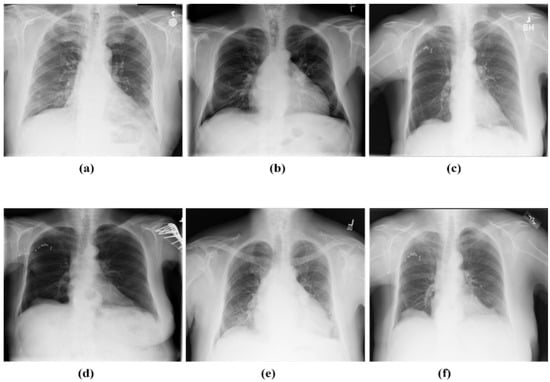

The authors of this study acquired a range of chest disorder datasets from several sources to train three pre-trained models, namely VGG-16, VGG-19, and DenseNet-169. Cohen et al. [57] created a GitHub repository, and it was through this that we were able to receive the CXR that were infected with COVID-19. CXR used in the creation of this database came from a wide variety of public and private institutions, both domestic and international, including hospitals and clinics. The average age of patients infected with COVID-19 was 55 years old; however, we do not currently have access to the complete set of metadata information. Through a search of the SIRM database [58], the TCIA database [59], radiopaedia.org [60], Mendeley [61], and the source on GitHub [62], we were able to collect a total of 2371 COVID-19-infected CXR. During the process of acquiring the CXR images collected for pneumonia, the RSNA [63] was utilized. This data set has a total of 5216 X-rays, of which 1349 were determined to be normal and the remaining 3867 revealed pneumonia. Utilization of the reference [64] allowed the acquisition of access to 5000 CXR of lung cancer. The CXR of healthy people was obtained from the Kaggle [65]. A total of 700 CXR images of TB were collected [66]. Figure 1 presents the sample images collected from the mentioned databases.

Figure 1. Sample images of CXR (a) TB, (b) LC, (c) COVID-19, (d) normal, (e) PneuTh, and (f) Pneu.